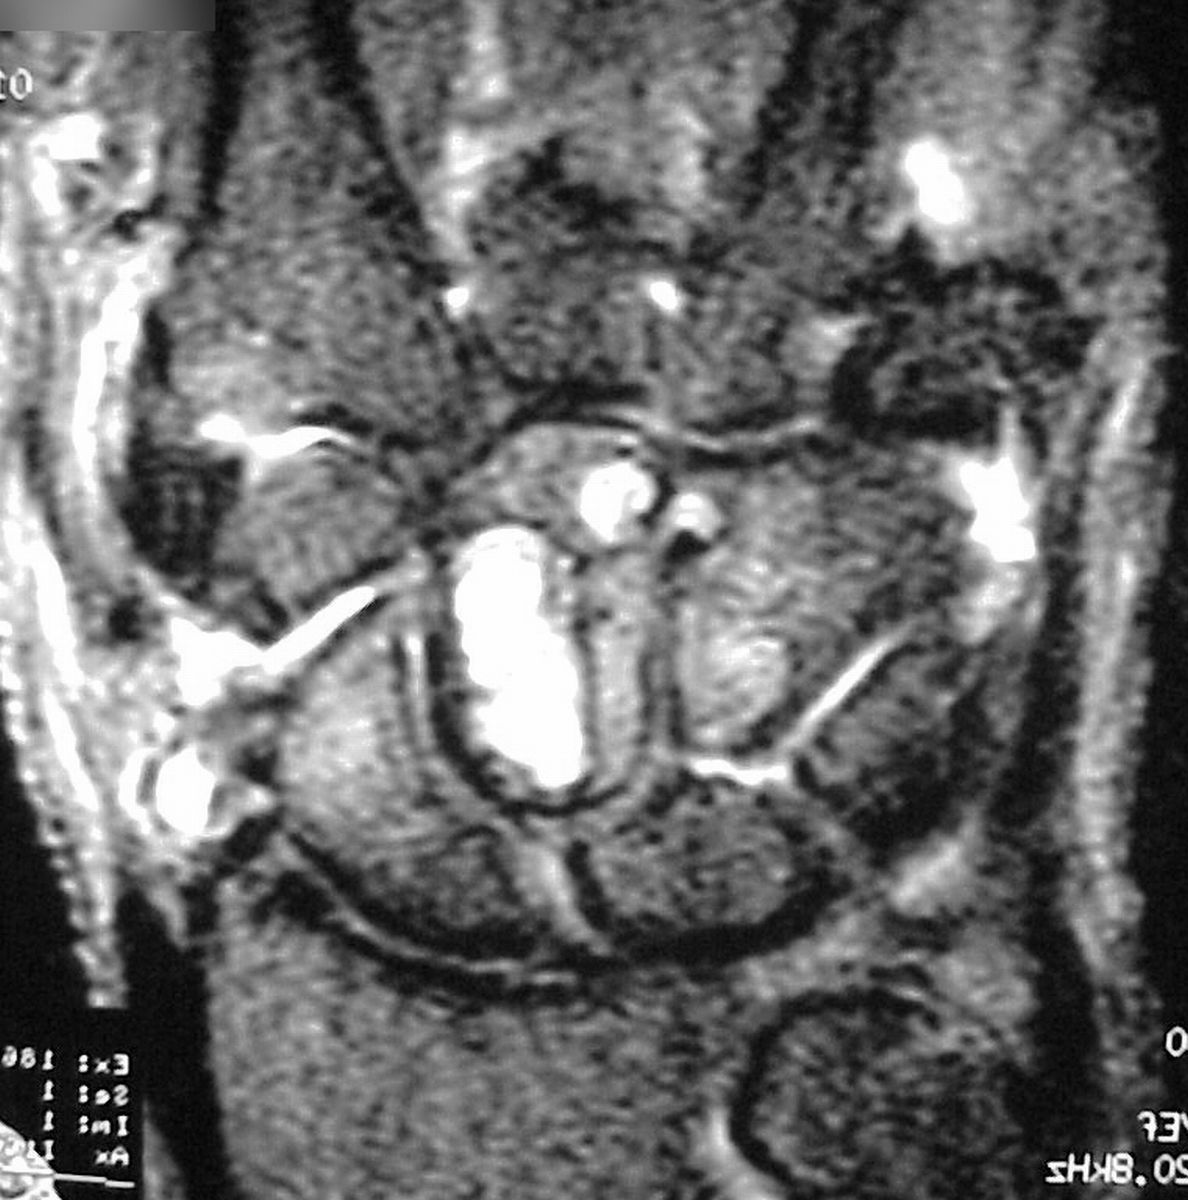

| MRI was

interpreted as inconclusive, differential including an

intraosseous cyst or giant cell tumor with cortical

thinning but no suggestion of malignancy. |